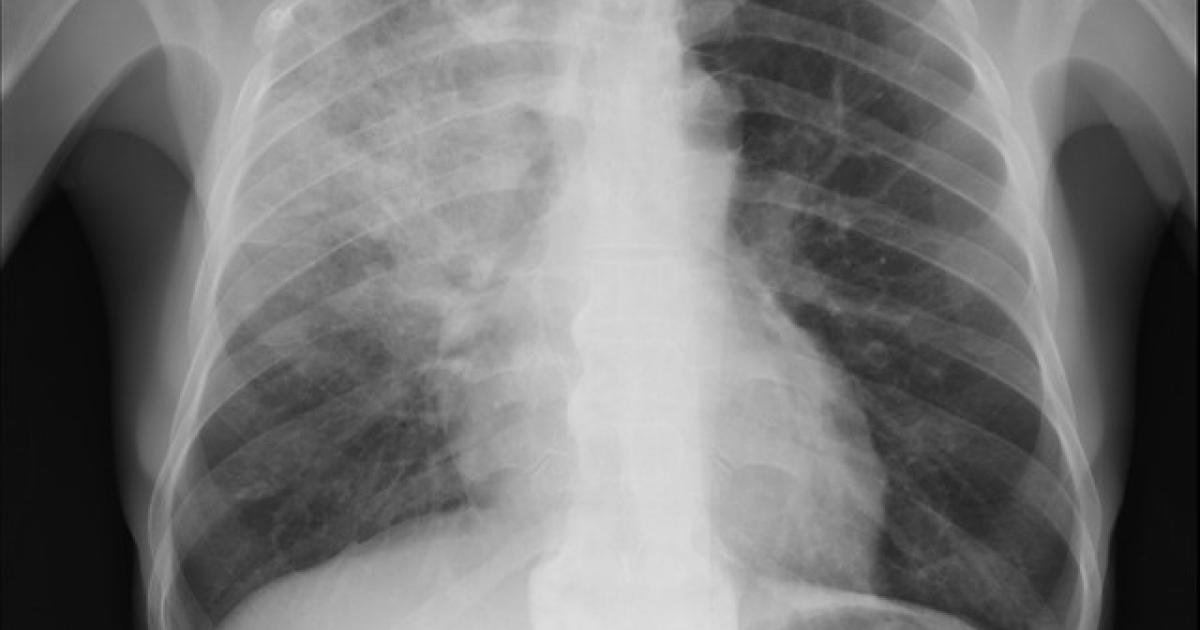

With that context in mind, the researchers studied patients treated in the hospital for pneumonia. The study involved the Michigan Hospital Medicine Safety Consortium, a network about 50% of Michigan’s nonfederal hospitals. [1] Patients all had a diagnosis of community or hospital-acquired pneumonia, evidence of pneumonia on examination and at least a 4-day hospital course of antibiotics. [2] Excessive days were defined as any course of treatment longer than national guidelines, and because of the vagaries in how this data is computed, you were compliant if the prescription was within a day of the recommendation. Outcomes came from medical records as well as 30-day follow up telephone conversations with patients. The study included 87% of eligible patients, roughly 6500 with a median age of 70, and about 75% had a community-acquired pneumonia. [3]

[2] This was necessary because the federal government has penalized hospitals for not starting antibiotics for “pneumonia” within an hour of admission. Pneumonia can be confused with other conditions, like heart failure, so to escape the penalty, hospitals start antibiotics and stop them once an ambiguous diagnosis is clarified a day or so later.